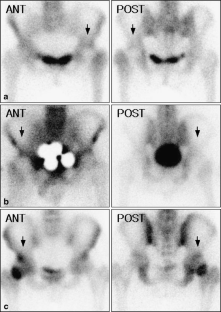

Fig. 2